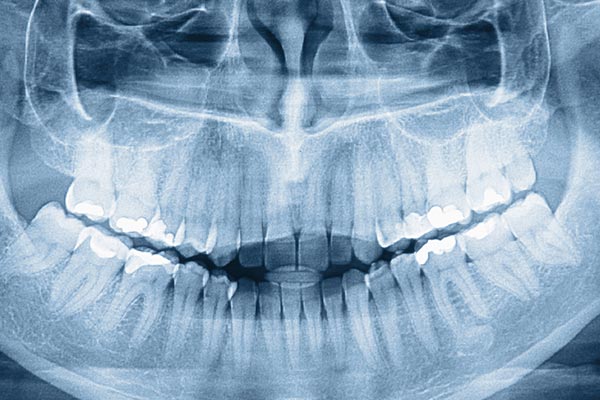

We use high-resolution digital radiography and advanced sensor technology to capture clear images of tooth roots, jaw relationships and overall oral anatomy. These images appear on-screen almost instantly, allowing clinicians to evaluate findings during the same appointment and discuss options with patients in real time. Digital imaging often includes panoramic or cephalometric views when needed to assess growth, alignment and skeletal relationships.

Digital images can be enhanced and reviewed from multiple angles without degrading the original data, which supports more accurate diagnosis and treatment planning. The immediate availability of images reduces the need for repeat exposures and helps the care team design predictable, individualized treatment sequences. At Longo Dietz Orthodontics we pair high-quality sensors with streamlined workflows so every diagnostic image directly informs excellent patient care.